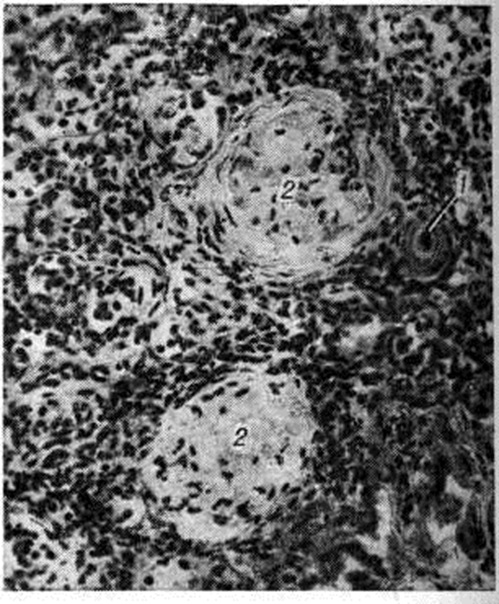

Гиалиноз наблюдается в соединительной ткани, строме органов и стенке сосудов (рисунок 2) в исходе плазматического пропитывания, фибриноидного набухания, склероза, хронический воспаления, некроза. В исходе плазматического пропитывания возникает Гиалиноз сосудов, чаще в артериальной системе. Наиболее распространён Гиалиноз мелких артерий и артериол (смотри Артериолосклероз). Гиалиноз артериол возникает в результате повреждения эндотелия, аргирофильных мембран и гладкомышечных волокон и пропитывания стенок сосуда белками плазмы крови, которые затем подвергаются ферментативным воздействиям, коагулируются и уплотняются, превращаясь в гиалиноподобное плотное вещество. Гиалиновые массы оттесняют кнаружи и разрушают эластическую пластинку, что ведёт к истончению средней оболочки; в результате артериолы превращаются в утолщённые плотные трубочки с резко суженным или полностью закрытым просветом. Гиалиноз мелких артерий и артериол, носящий системный характер, но наиболее выраженный в почках (рисунок 3 и 4), головном мозге, сетчатке глаза, поджелудочной железе, коже (рисунок 5), особенно характерен для гипертонической болезни (гипертонический артериологиалиноз). Нередко системный Гиалиноз артериол и мелких артерий наблюдается при хронический васкулярном гломерулонефрите и симптоматической артериальной гипертензии любого генеза. Распространённый Гиалиноз артерий эластического и эластическо-мышечного типов постоянно наблюдается при атеросклерозе, диабете и отражает процессы плазморрагии и инсудации, характерные для этих заболеваний. Местный Гиалиноз артерий как физиологическое явление встречается в селезёнке взрослых и пожилых людей, отражая функционально-морфологически особенности селезёнки как органа депонирования крови.

В исходе фибриноидного набухания, ведущего к деструкции коллагена и пропитыванию ткани плазменными белками и полисахаридами, соединительнотканные пучки разбухают, теряют фибриллярность и сливаются в однородную плотную хрящеподобную массу; клеточные элементы сдавливаются и подвергаются атрофии. Подобный механизм развития Гиалиноз собственно соединительной ткани и сосудистой стенки особенно часто наблюдается при заболеваниях с иммунными нарушениями. Так, системный Гиалиноз соединительной ткани и стенок сосудов выражен при коллагеновых болезнях: Гиалиноз клапанов сердца, стромы миокарда — при ревматизме, Гиалиноз синовиальных оболочек — при ревматоидном артрите, Гиалиноз кожи — при склеродермии, Гиалиноз стенок сосудов — при узелковом артериите и системной красной волчанке. Таков же механизм распространённого Гиалиноз почечных клубочков при иммунокомплексном гломерулонефрите. В этих случаях гиалин строится на иммунных комплексах, что подтверждает роль иммунологический механизмов в развитии Гиалиноз. Местный Гиалиноз может завершать фибриноидные изменения в дне хронический язвы желудка, в ткани червеобразного отростка при аппендиците, а также в очаге хронический воспаления.